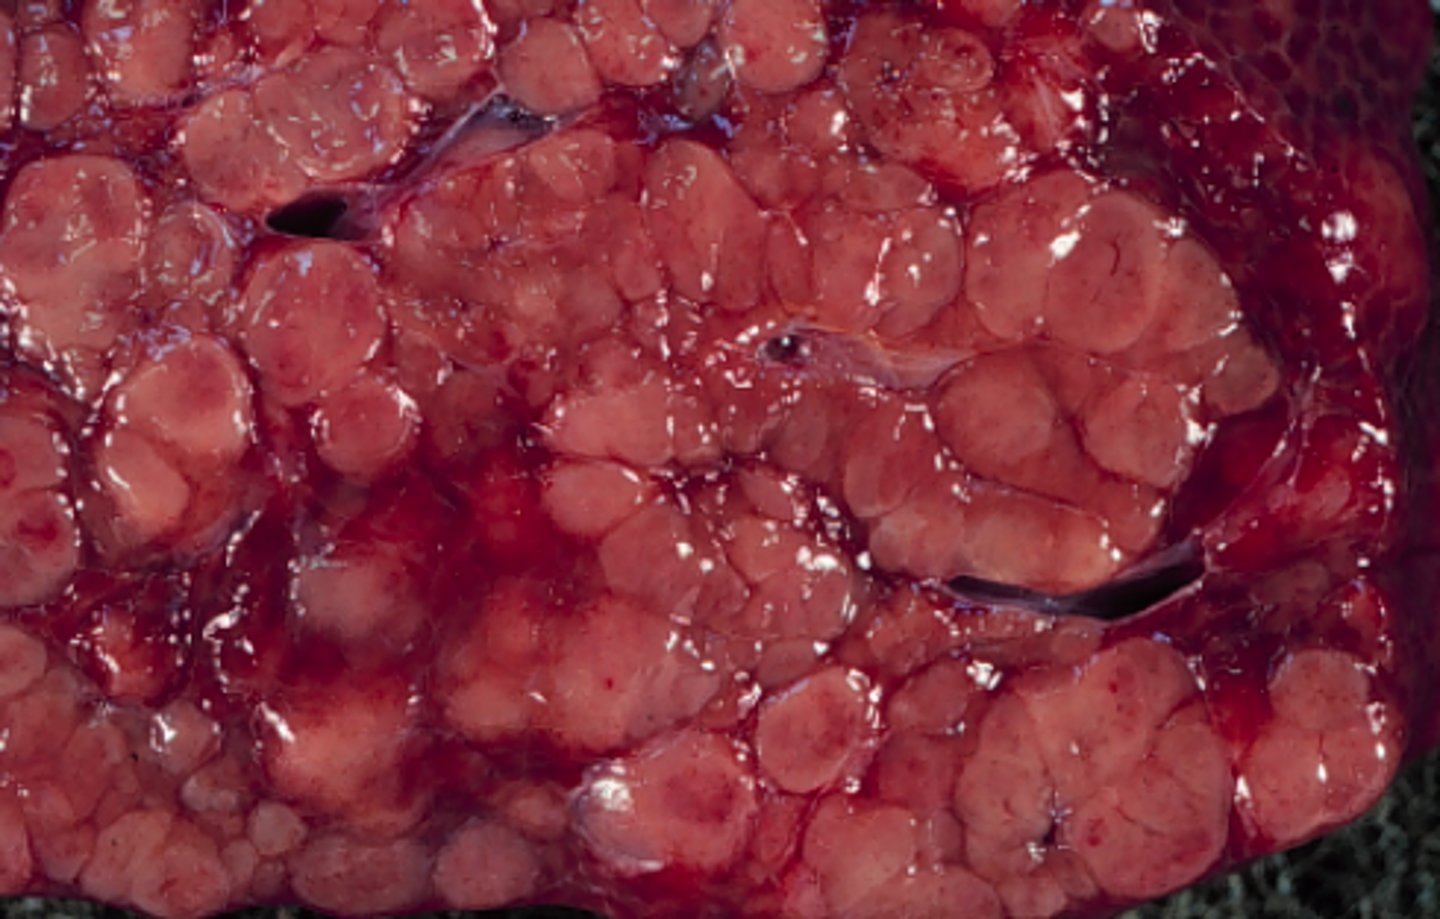

Dissimineret multicentrisk nodulær lymfosarcom

Lever fra svin, hvad er den patoanatomiske diagnose?